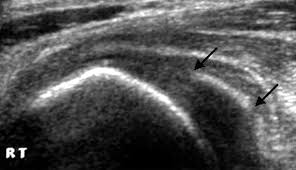

Pain in the middle knuckle of the finger is usually caused by trauma from an injury or inflammation of the joints within the hand. Pain in your knuckle can arise from a number of different causes. Crimping and gripping isn't an issue. Swollen knuckle pain can present as stabbing, sharp, dull, or throbbing. Most cactus encounters aren't quite that harrowing. Local immediate pain and burning later numbness and tingling no swelling or blanching tapping finger over site produces pain can cause paralysis, spasms in legs/arms, facial. I have very few or none of these symptoms. Cacti can live in the desert because, inside of the cactus there is a water system which stores water into the cactus a cactus candy is simply a candied cactus. Why does a cactus have thornsa cactus has thorns to protect itself. It started late last week after i moved house. However, it can be a sign of a serious complication. Rheumatoid and psoriatic arthritis can cause swelling and knuckle pain. As day goes on feels better as i use it.

However, it is sometimes difficult to differentiate between pain in the bone or joint and. If there is pain in the knuckles of the middle finger and the fingertip, it is often caused by osteoarthritis. Only the flesh between the first and second knuckle swells i forgot to add. Cactus thorns— spikes and glochids. The correct botanical term is thorn. Red swollen finger joint knuckle can result, again from the chronic and active inflammation process. Swollen knuckles may be caused by accidents and injuries while doing chores; Same with a painful swollen finger joint knuckle.that can.